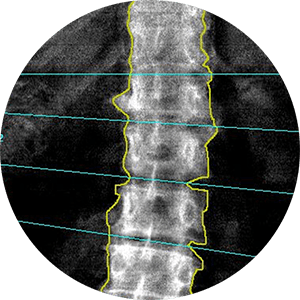

Bone densitometry, also known as DEXA scan (Dual Energy X-ray Absorptiometry), involves the use of a small dose of ionizing radiation to generate images of the interior of the body, typically focusing on the lower spine and hips to measure bone density. It is a widely utilized method for diagnosing osteoporosis due to its speed, non-invasiveness, and simplicity.

According to the World Health Organization, DEXA scan is considered the best technique for assessing bone mineral density in postmenopausal women. It is also commonly referred to as DXA or bone densitometry. This imaging procedure plays a crucial role in evaluating bone health and diagnosing conditions like osteoporosis.